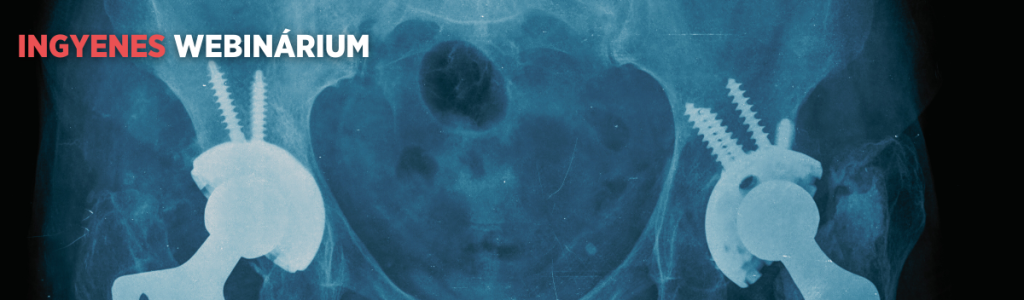

„Semmi sem tart örökké!” – sajnos ez igaz az évtizedekkel korábban beültetett protézisekre is. A jó hír viszont az, hogy ma már lehetséges ezek részleges vagy akár teljes cseréje. Sőt, ha a páciens vállalja, és egészségi állapota is lehetővé teszi, precíz tervezéssel és összehangolt csapatmunkával akár mindkét oldali protézis is beültethető egy műtéti altatás alatt.